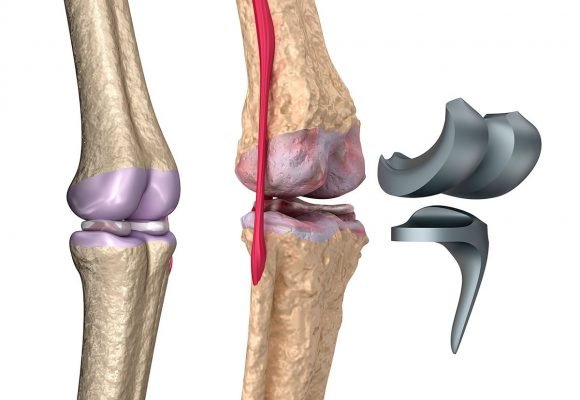

En qué Casos Utilizar Prótesis en Rodilla: Cuando existen daños severos en las rodillas, se tiende a hacer una cirugía en la que se inserta una prótesis total de rodilla. Esta nueva rodilla es de materiales espaciales que aliviarán el dolor y harán que se mantenga la función de la misma para el paciente.

Osteoartritis u Artrosis: es una enfermedad que acaba con el tejido que recubre al hueso en sus extremos. Como estos huesos están articulados con otros, y ya no está ese tejido que permite que se resbalen los unos con los otros, entonces comienzan a tener roces que no permiten que la articulación funcione. Comienzan a desgastarse el hueso y causa dolor e hinchazón.